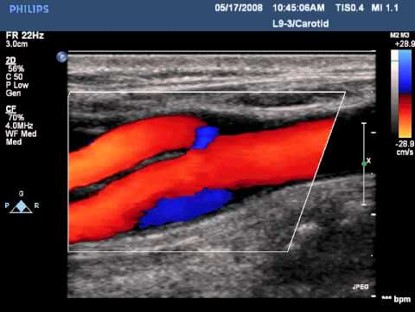

Color Doppler

Color Doppler Imaging visualizes the blood flow within a defined area. In a similar manner to Pulsed Wave Doppler (PWD), Color Doppler utilizes intermittent sampling of ultrasound waves to determine the Doppler shifts from moving blood. Unlike PWD, CFD simultaneously interrogates multiple sample volumes represented by pixels across an array of scan lines. The resulting flow velocity and direction are color-coded onto a grayscale image, typically with red indicating flow towards the transducer and blue indicating flow away. When the Nyquist limit is reached, aliasing occurs, causing apparent flow direction reversal.

Figure 3. Color Doppler in carotid bifurcation